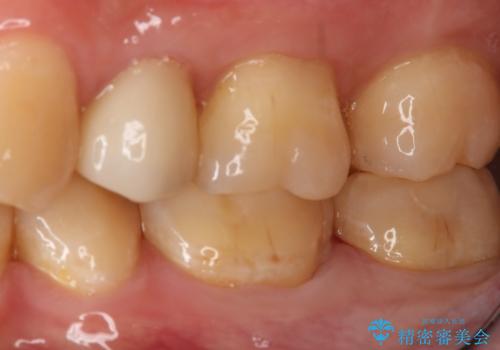

- 左下7番のCR劣化を自費治療にて希望された患者様です。

切削量を考慮してセラミックインレーでの治療を選択しました。

CR直下と隣接面にう蝕が進行していたので、除去した上で形成、印象しています。